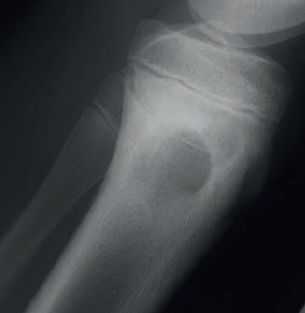

Рентгенограмма. Абсцесс Броди.

Неполностью вылеченный остеомиелит приводит к полостям, типично расположенным в метафизах длинных трубчатых костей. Он называется абсцесс Броди.